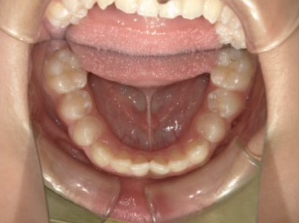

治療中⑨ 中3:14y4m

モノブロック装置で左上八重歯が改善しました

今後、必要によりマルチブラケット法へ移行予定です